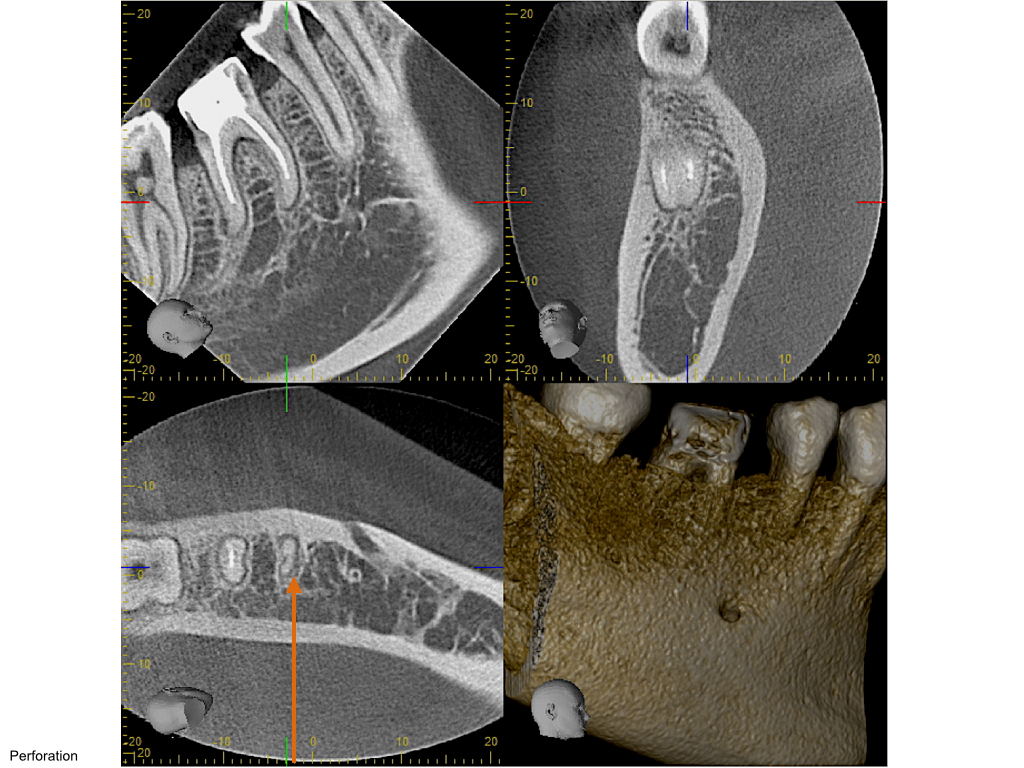

Saving hopeless teeth (36)